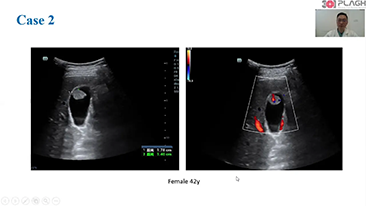

?? ?? ?? ??? ?? ?? ?? ???? ?? ???? OBG ?????? ?????. ?? ??, ?????(CNS) ??? ?? ?? ??? ?? ? ?????. ???? ?? ??? ?? ??? ??? ??? ?? MSP? 2D ????? ?? ???? ?????. ??? ?? ?? ? ??? ??? ???? ?? ???? ? ????.